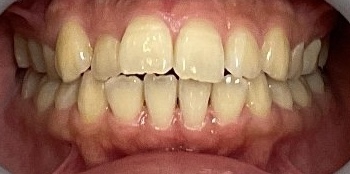

症例1 前歯の歯並びが後戻りによって出てきてしまったしまったケース(中等度)

10年ほど前のワイヤー矯正後に、保定装置をつけていなかったことが原因で前歯が後戻りしています。

- 治療方法 インビザライン上下+形態修正

- 治療期間:1年

- 治療費用 ¥759000(税込)

- 治療のリスク・デメリット 保定装置をしないと後戻りする

Before

After